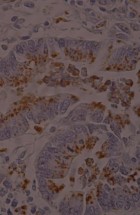

Делатност Одељења обухвата истраживачки и специјалистичко – стручни рад. Одељење се бави клиничком, патоанатомском, патохистолошком, имунохистохемијском и молекуларном дијагностиком обољења домаћих и дивљих животиња, као и патологијом репродукције. Рад на одељењу је организован кроз теренске и лабораторијске активности.

- Патохистолошка, цитолошка, имунохистохемијска и молекуларна дијагностика;